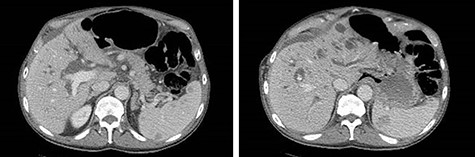

Eleven months after PD, the patient presented to the emergency department with abdominal pain, distension and obstipation. He was hemodynamically stable, with physical examination notable for large incisional hernia with severe abdominal distension and tenderness without peritonitis. Computed tomography scan of the abdomen demonstrated a coffee-bean shaped cecum in the left upper quadrant with dilated colon and evidence of mesenteric swirling in the right lower quadrant, consistent with cecal volvulus (Fig. 2). The patient was taken to the operating room for urgent exploration.

CT of the abdomen and pelvis demonstrating coffee-bean shaped cecum in left upper quadrant dilated to 12 cm, consistent with cecal volvulus.